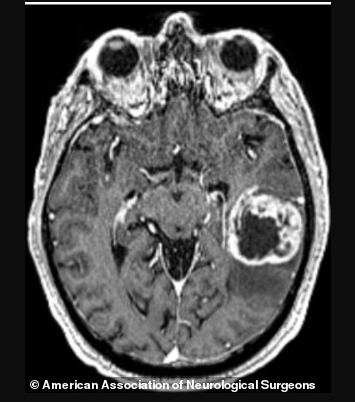

绝大多数患有脑瘤的人于1975至2000年间毕业,但最近的一起案例则是2014年刚刚毕业的。这些患者所诊断包括几种类型的原发性脑肿瘤,包括胶质母细胞瘤等。这种癌症极为罕见,根据美国神经外科医师协会的数据,胶质母细胞瘤的发病率为10万分之3.21。

胶质母细胞瘤是一种最常见的脑部原发性癌症,临床也常简称“胶母”,是胶质瘤的一种,也称“胶质瘤四级”,约一半的胶质瘤患者为胶质母细胞瘤,是神经外科最常见的恶性肿瘤。这是一种能迅速恶化的癌症。